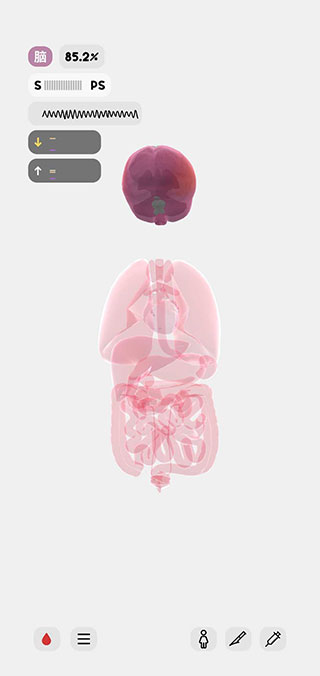

这是一款很严谨的科普类游戏,因此很多玩家都不知道生命人体模拟器怎么玩,为此小编也为大家带来了这篇玩法攻略,希望可以帮助到大家。1、进入游戏后,我们首先需要创建一个人体模型,左上角为该模型的基本构成信息,它们只能点击切换,并不能具体自定义,之后再点击右上角的创建按钮。

2、这时候我们可以看到人体模型已经成功创建,显示的是人体各个器官的透视图,左上角显示是人体的各个主要信息参数指标。

3、任意点击其中的一个指标,会显示该指标的说明信息和正常范围,点击下方的了解更多按钮,会打开浏览器,跳转到更详细的科普说明页面。

4、我们用手指向屏幕两边进行拖动,会将人体器官分开显示,这样会更有助于我们查找对应器官,点击屏幕中央,器官又会聚拢在一起。

5、我们还可以滑动手指来旋转人体模型,例如下图所示,就是从侧面观察到的模型状态。

6、点击模型中的任意一个器官,它就会产生高亮效果,并且左上角的状态栏会切换显示为该器官的参数指标。

7、再次点击该器官,会显示它的具体说明信息,并在模型中标注出器官构成,点击下方的了解更多按钮,同样会进行浏览器跳转。

10、点击右下角的人体图标,可以为该模型设置不同的状态,其中包括了生理学、心理学和病理学三方面,可以观察人体在不同状态下的反应。

11、点击右下角的手术刀图标,可以为模型进行相应的治疗措施,其中包括了急救术和切除术等。

12、点击右下角的注射器图标,可以为模型注射不同的药物以观察其反应,或者观察模型进食后的情况。